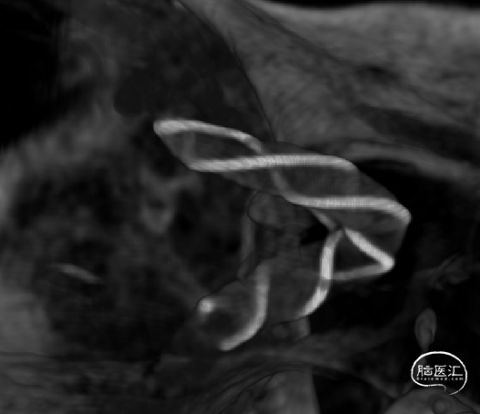

Vaso I.A. CT检查,支架完全打开,位置及贴壁良好,动脉瘤内部分造影剂滞留